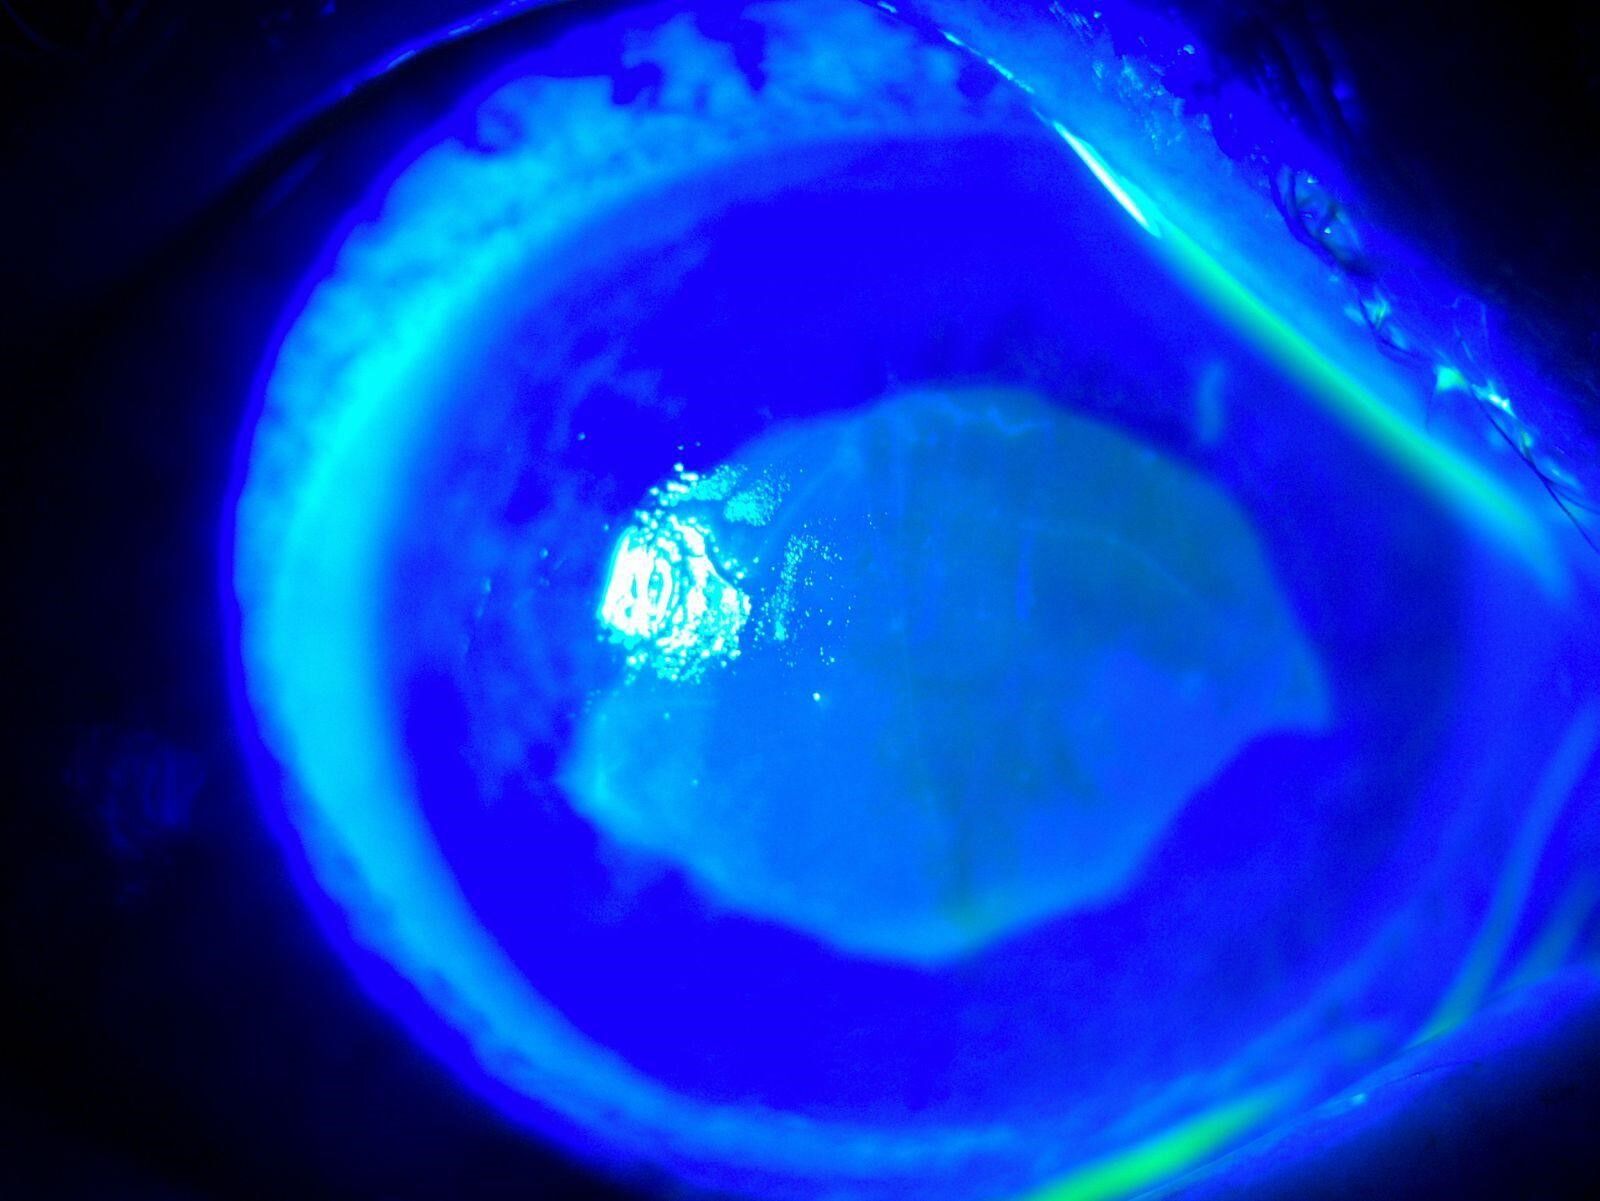

Göze yabancı cisim, kimyasal madde kaçması ya da enfeksiyon durumlarında gözü temizlemek amacıyla uygulanan göz yıkama tedavisi gerçekleştirildi. Yaklaşık 2 haftalık tedavinin ardından hasta sağlığına kavuştu. Doç. Dr. Yılmaz, hastasının yaşadığı süreç ve tedavisine ilişkin bilgi verdi. Yılmaz, hekim önerisi olmadan herhangi bir ürün kullanılmaması gerektiğine dikkat çekerek önemli uyarılarda bulundu. Öte yandan hastanın göz bebeğinin beyazlığı ve göz akının ise kızardığı hali fotoğraf karesine yansıdı.

Hastasına ilişkin bilgi veren Doç. Dr. Ömer Faruk Yılmaz, "52 yaşında bir bayan hastamız, kızının önerisiyle gözlükten kurtulmak için 2 gözüne taze kırlangıç otu suyunu sıkarak damlatmıştı. Kırlangıç otunu sıktığımız zaman sarı bir sıvı akmaktadır. Hastamız o sıvıyı her 2 gözüne damlatmış. İlk aşamada gözünde yanma, batma oluyor, birkaç saat sonra her 2 gözünü açamıyor, tamamen göremez hale geliyor. Bize geldiğinde hastamız 2 gözünü açamaz haldeydi. Göz muayenesinde 2 gözün korneasının tamamen tahrip olduğunu gördük. Korneanın epiteli tamamen soyulduğu için hastamızın gözünde pü şeklinde akıntı mevcuttu. Hasta, ‘Acaba göremeyecek miyim, gözüme ne oldu, bu ilacı neden damlattım?' diye sorgulayarak gelmişti" dedi.

Uyguladıkları tedaviye yönelik konuşan Doç. Dr. Yılmaz, "Göz uyuşturucu damla ile hastanın gözünü açtık, muayenemizi yaptık. Kornea epiteli tamamen deforme olmuştu. Her 2 gözünü 25 dakika yıkadık, gerekli tedavi ve damlalara başladık. Yaklaşık 6-7 ay önce oldu, toplam tedavimiz 10 gün- 2 hafta süresince devam etti. Tedavi sonunda 2 gözünde görmesine tamamen ulaştı. Hasta ilk başta çok korkmuştu, 2-3 gün boyunca bayağı sıkıntılar yaşadı. İlk 2 gün hatta ağrıdan, yanmadan, batmadan hasta uyuyamadı, iyileştikten sonra çok mutlu olmuştu. Sosyal medyada özellikle son zamanlarda kırlangıç otu çok yaygınlaşmaya başladı. Literatürü taradığım zaman kırlangıç otunun tarihte birçok hastalıklara; cilt, mide hastalıkları gibi hastalıklara geleneksel olarak kullanıldığını gördüm. Bitkisel ilacın içeriği faydalı olsa bile yüksek doz damlatılması gözümüze zarar verebilir" diye konuştu.

"Kırlangıç otu kullandı, hastamız göremez hale geldi eğer tedavi edilmeseydi sonucun ne olacağını bilemiyoruz fakat tedavi sonucunda hastamız iyileşti. Gözlerinin fotoğrafını çektirdim, kırlangıç otunun geçişini gösterdik. Tedavi edilmediği zaman göz içinde belki de körlüğe ulaşabilecek şekilde istenmeyen yan etkilere yol açabilir. Yüzlerce farklı ot olabilir, yanlışlıkla faydalı bir ot damlatacağız diye zararlı bir otu damlatabiliriz. Göze direkt damlatılması steril değildir, göze zarar verebilir, enfeksiyon oluşturabilir. Faydalı bile olsa Sağlık Bakanlığı ruhsat vermeden, ilaç formatına dönüştürmeden, uygun dozajlar ayarlanmadan ve göz hekiminin önerisi olmadan göze herhangi bir bitkisel ilaç damlatılmasını önermiyoruz."